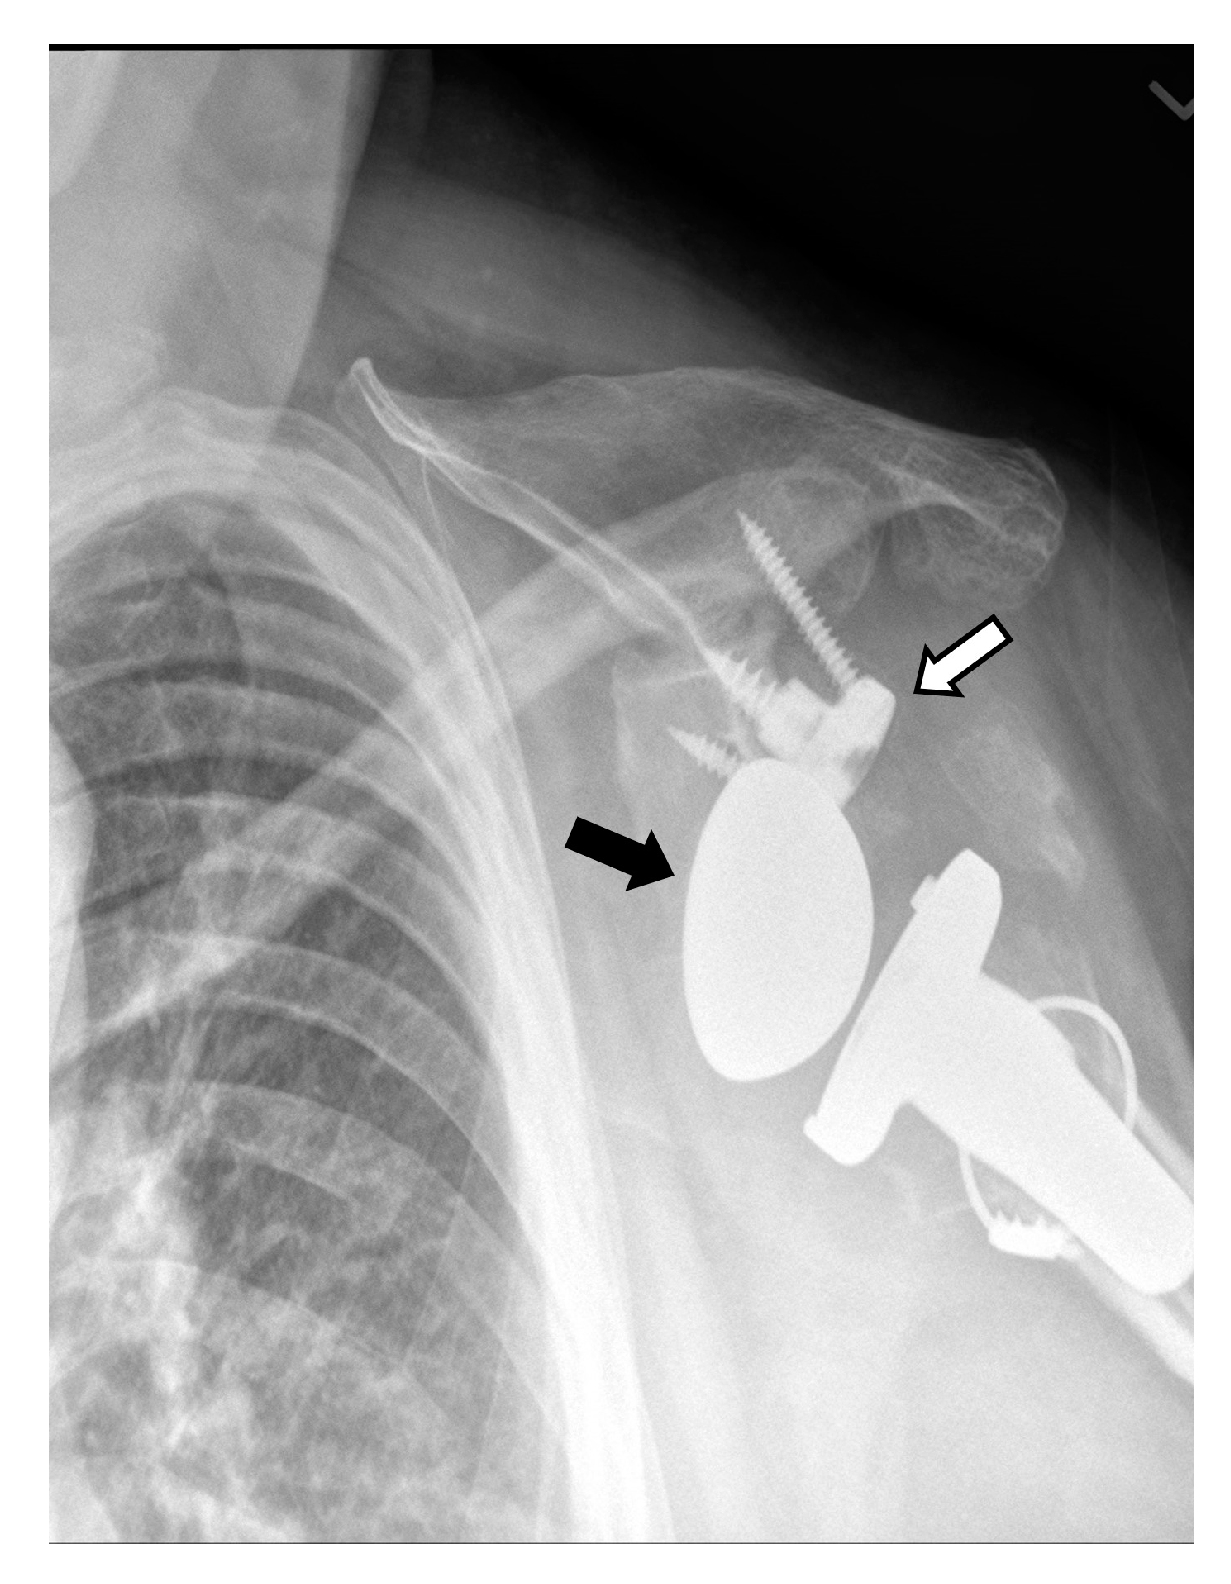

4.2.1. Loosening and Hardware Dissociation

4.3. Unique Complications

5.3. Revision Shoulder Arthroplasty